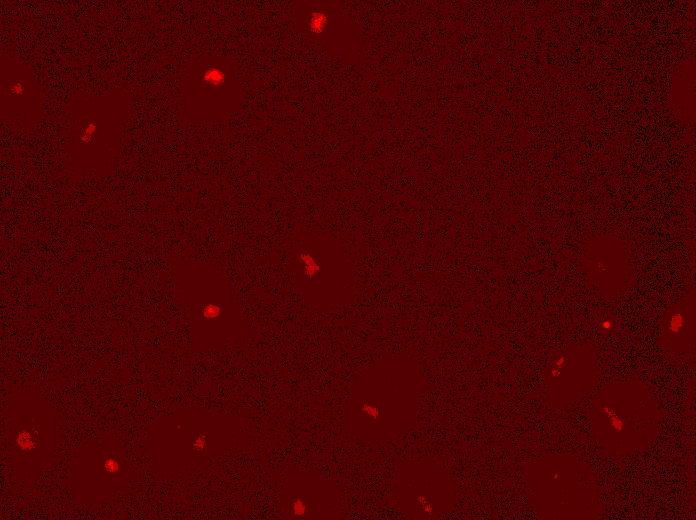

Overlay